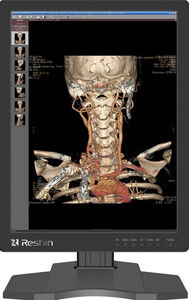

亮度(cd/m²): 900 cd

响应速度: 16 ms

用电量: 50 W

... 高亮度和高对比度的结合,形成了明显的深度感,是定位病灶的完美选择。 焦点观察聚光灯 启用聚光灯后,系统会将全屏调暗,通过软件捕捉光标的坐标,并将以光标为中心的圆形区域或矩形区域以最高的校准亮度高亮显示。这就达到了类似于舞台上的聚光灯的效果,突出了病灶并协助诊断。 4.X射线胶片查看器 该显示器有一个内置的灯箱模式。通过磁性胶片夹夹住胶片,并通过快捷键进行快速操作,医生可以方便地在显示器上阅读胶片。 5.环境亮度适应性 通过环境光补偿和校正系统,瑞信可以更好地适应人眼的观察能力,显示图像,并可应用于各种亮度环境 ...

Reshin Monitors